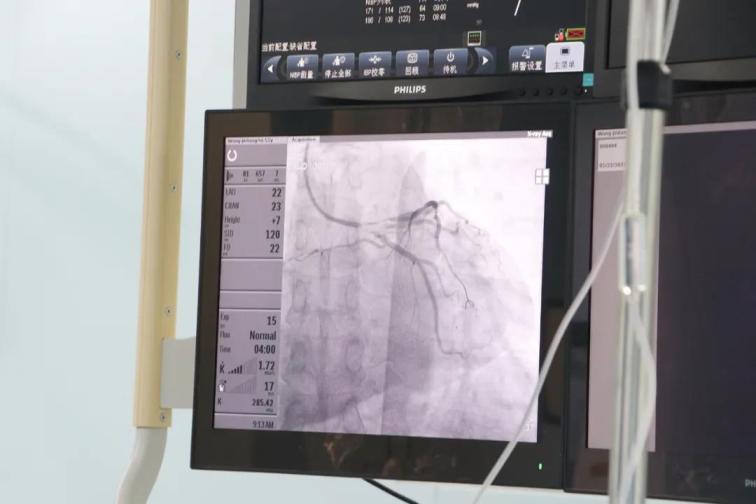

患者王某,男性,52歲,因胸悶半年,加重伴呼吸困難6天于5月8日入院,否認(rèn)高血壓和糖尿病史,外院256排CT提示:左前降支近段局限性中度狹窄,不能完全排除重度可能。入院后行心臟冠狀動(dòng)脈造影檢查,結(jié)果提示前降支近段狹窄90%,中段狹窄70%,合并心肌橋,遠(yuǎn)段狹窄80%,患者及家屬不接受植入支架,在給予前降支近段充分預(yù)處理后,使用藥物涂層球囊送至病變部位,緩慢加壓,持續(xù)擴(kuò)張45秒,術(shù)后患者癥狀消失,并于5月27日痊愈出院。